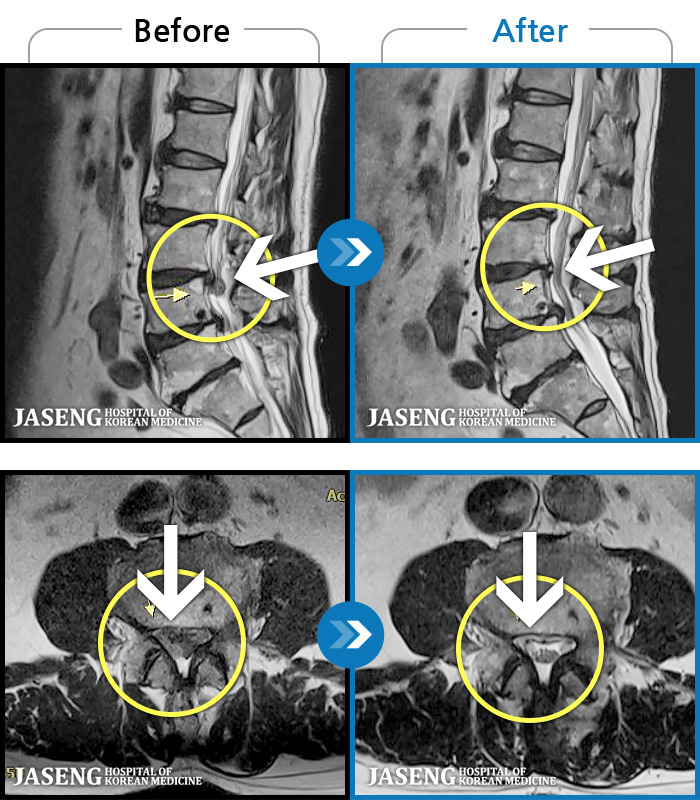

MRI 치료사례

양측 허리부터 골반까지 묵직한 통증, 우측 다리 방사통이 심하여 내원하셨습니다.